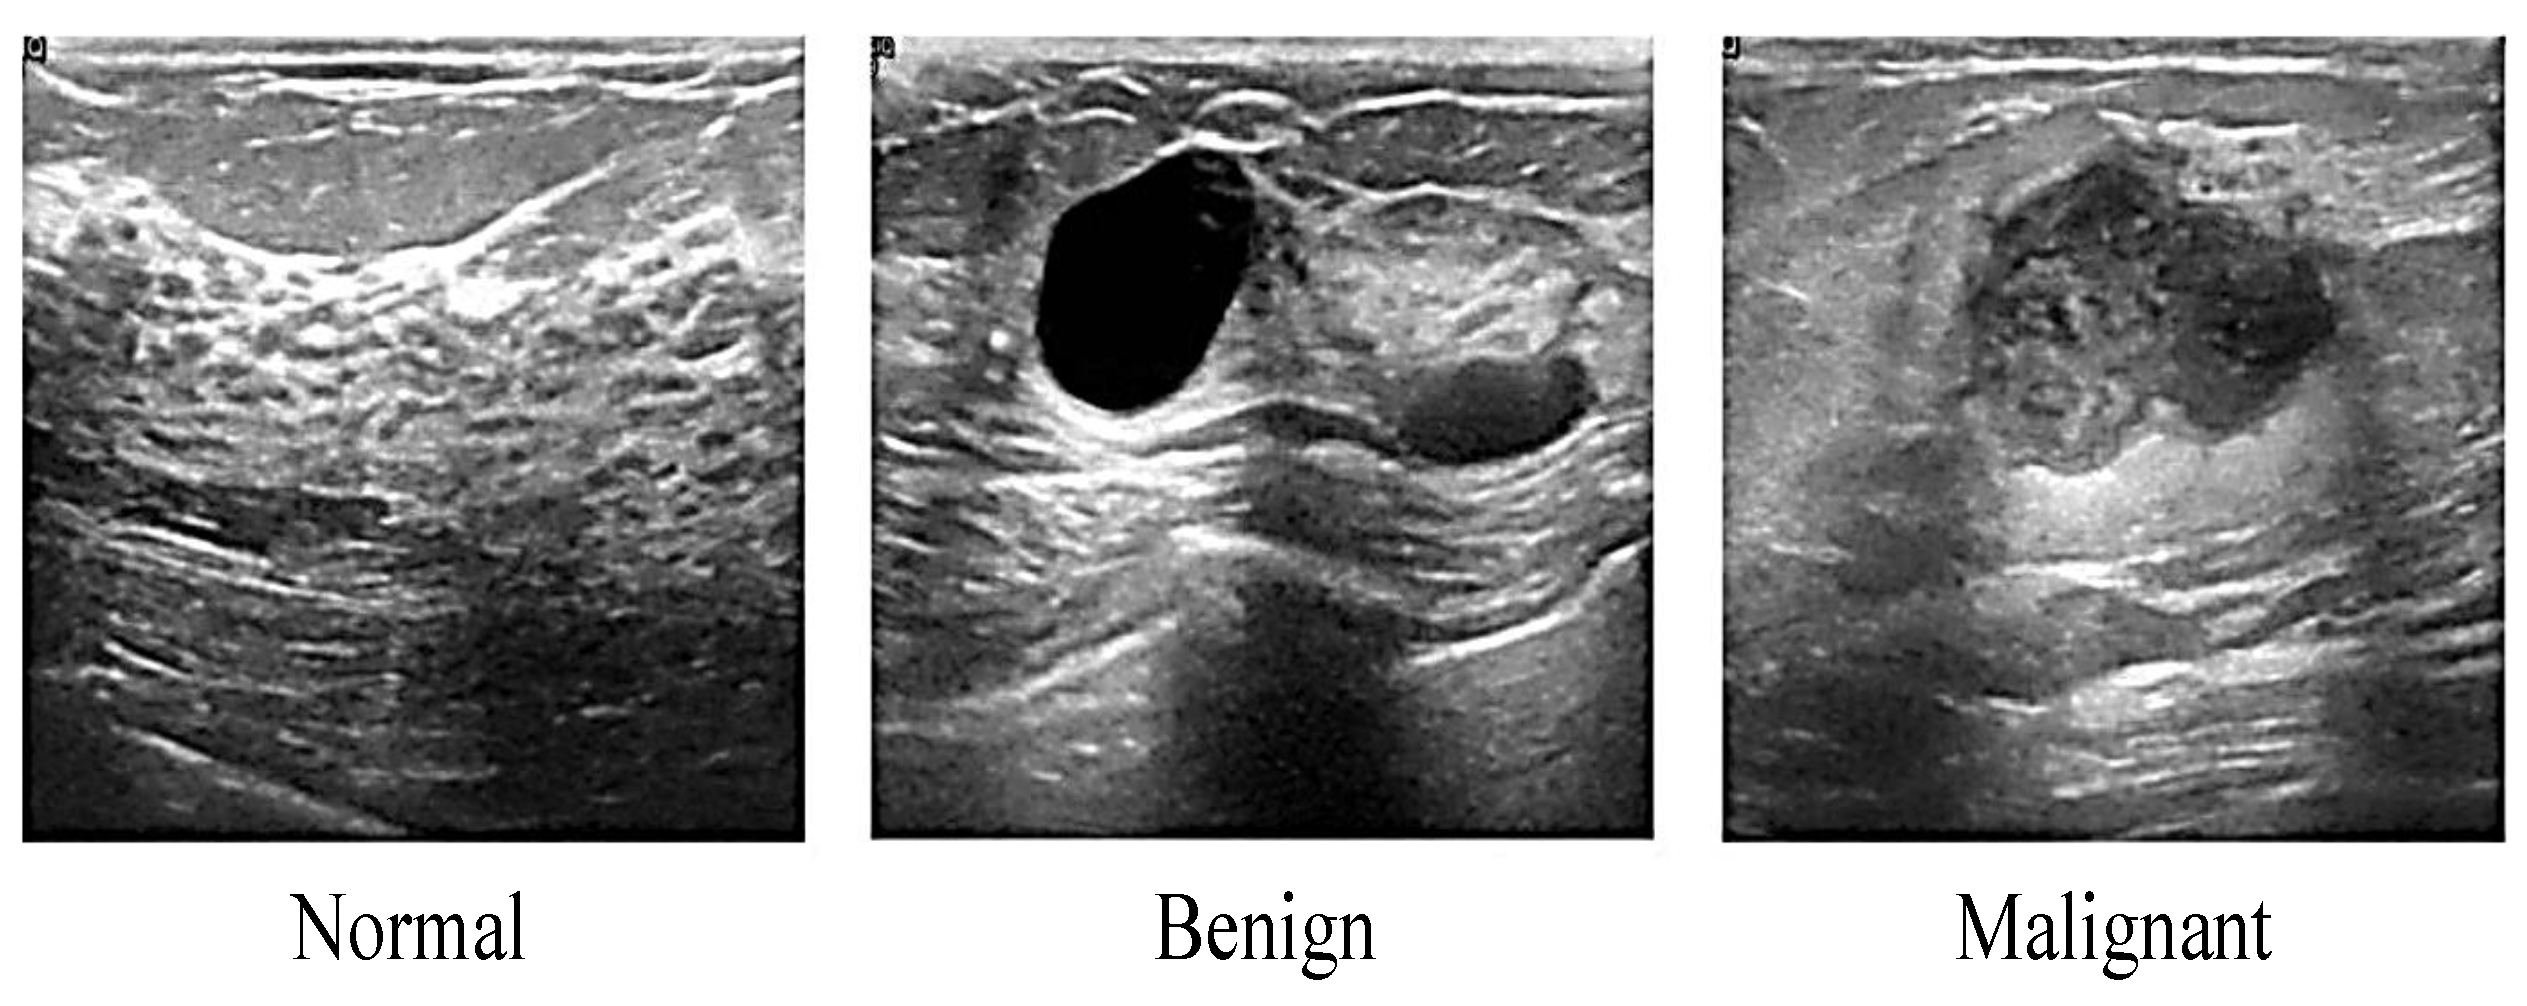

2.1.1. Ultrasound

- Al-dhabyani, W.; Gomaa, M.; Khaled, H.; Fahmy, A. Dataset of breast ultrasound images. Data Brief 2019, 28, 104863. [Google Scholar] [CrossRef] [PubMed]

- Ouyang, Y.; Tsui, P.; Wu, S.; Wu, W.; Zhou, Z. Classification of benign and malignant breast tumors using H-Scan ultrasound imaging. Diagnostics 2019, 9, 182. [Google Scholar] [CrossRef]